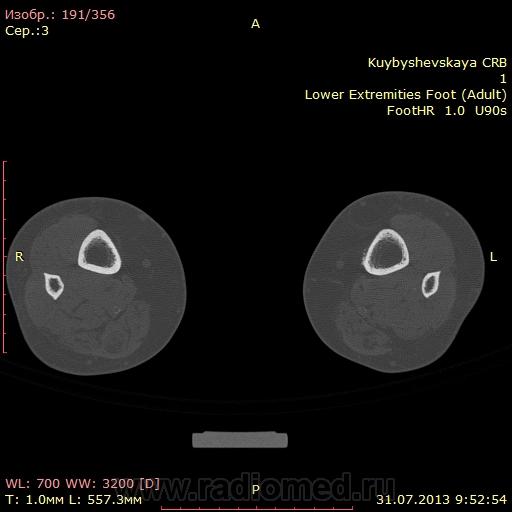

женщина. 69 лет. жалобы на боли в нижней трети голени слева в течении месяца. по снимкам врач написал периостит(к сожалению фотоаппарата нет под рукой)В ближайшее время травм не было. мне досталась только карточка. Пациента не видел. Помогите с диагностикой. вроде бы на зло не похоже. или ошибаюсь?

DICOM

На зло непохоже, нет мягкоткотканного компонета. Передне-медиальная поверхность голени - самое место для травмы. Только термин "периостит" мне тоже не нравится, написал бы - локальное обызвествления мягких тканей, вероятнее всего посттравматического характера.

По снимкам описал бы как обызвествившуюся гематому, а по КТ больше тянет на экзостоз, только основание очень широкое.